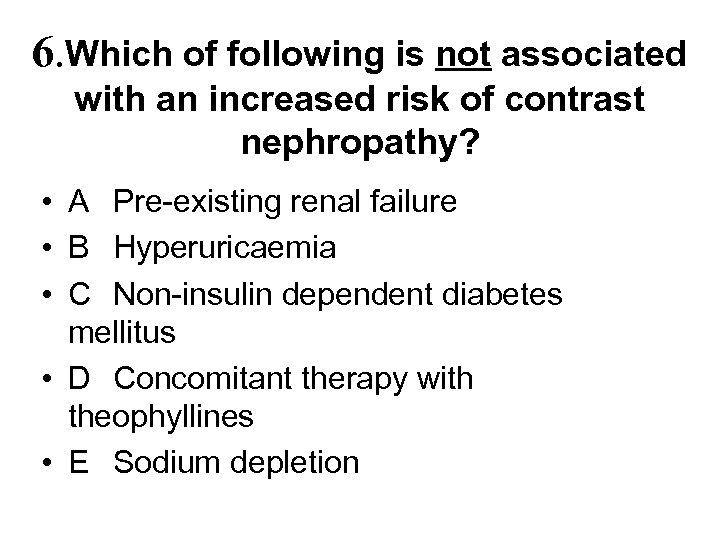

6. Which of following is not associated with an increased risk of contrast nephropathy? • A Pre-existing renal failure • B Hyperuricaemia • C Non-insulin dependent diabetes mellitus • D Concomitant therapy with theophyllines • E Sodium depletion

6. Which of following is not associated with an increased risk of contrast nephropathy? • A Pre-existing renal failure • B Hyperuricaemia • C Non-insulin dependent diabetes mellitus • D Concomitant therapy with theophyllines • E Sodium depletion

6. Which of following is not associated with an increased risk of contrast nephropathy? • • A Pre-existing renal failure B Hyperuricaemia C Non-insulin dependent diabetes mellitus D Concomitant therapy with theophyllines • E Sodium depletion

6. Which of following is not associated with an increased risk of contrast nephropathy? • • A Pre-existing renal failure B Hyperuricaemia C Non-insulin dependent diabetes mellitus D Concomitant therapy with theophyllines • E Sodium depletion